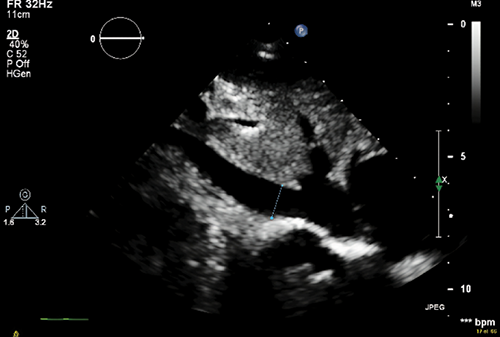

The Effect of COVID-19 Infection on Ventricular Pacing Threshold among Patients with Pacemakers: A Retrospective Observational Study

Komsing Methavigul, MD¹

114